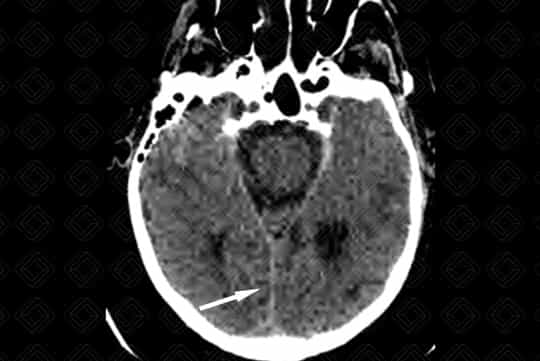

Texto alternativo para a imagem Figuras 1 e 2. Créditos: Dra. Elazir Mota - Rio de Janeiro/RJ

Descrição da lesão (figuras 1 e 2): Tomografia computadorizada de crânio sem contraste venoso. Áreas de hemorragia subracnoide córtico-subcorticais nas regiões temporal esquerda e temporo-parietal direita (setas vermelhas). Há ainda moderada hiperdensidade do seio reto e tentório cerebelar, sugerindo sangramento (setas brancas).